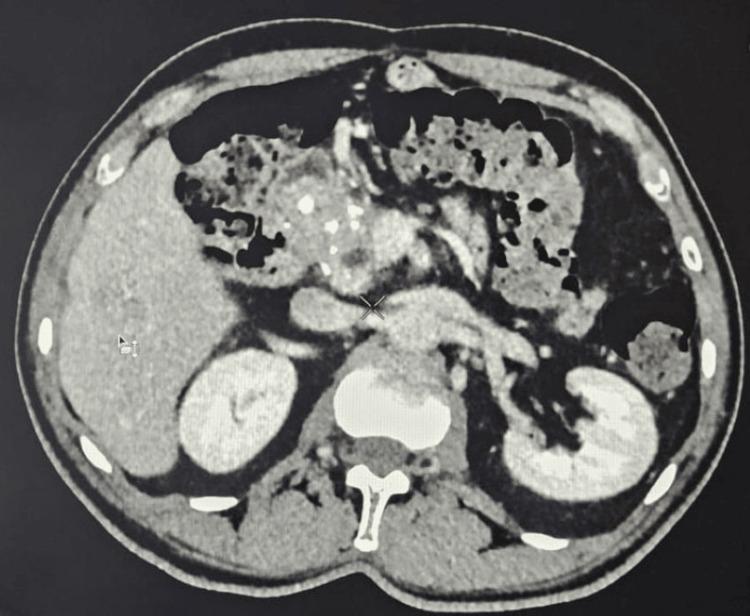

We report a rare case of a 59-year-old male patient with poorly controlled diabetes mellitus who presented with concurrent hepatic and pulmonary abscesses. Imaging revealed a large septated hepatic lesion and multiple bilateral pulmonary cavities. Cultures from blood and drained hepatic pus confirmed . Despite the lack of genomic testing, the clinical course was consistent with invasive syndrome (IKPS). The patient was treated successfully with prolonged intravenous and oral amoxicillin-clavulanate over six months, along with percutaneous drainage of the hepatic abscess. Follow-up imaging demonstrated near-complete resolution of both liver and lung lesions. This case highlights the importance of early source control and extended culture-guided antibiotic therapy in managing severe invasive infections in immunocompromised patients.

我们报告了一例罕见病例,一名59岁男性糖尿病患者,血糖控制不佳,同时出现肝脓肿和肺脓肿。影像学检查显示肝脏有一个大的分隔性病变以及双侧多个肺空洞。血液和引流的肝脓液培养结果证实了……。尽管缺乏基因组检测,但临床过程符合侵袭性……综合征(IKPS)。患者接受了为期六个月的延长静脉和口服阿莫西林 - 克拉维酸治疗,并对肝脓肿进行了经皮引流,治疗成功。随访影像学检查显示肝脏和肺部病变几乎完全消退。该病例强调了在免疫功能低下患者中,早期源头控制和延长的培养指导抗生素治疗在管理严重侵袭性……感染中的重要性。